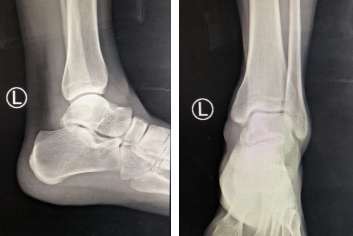

3月28日,家住徐州县区的张宇(化名)干活时不慎从1米高处摔下,左踝部受力,即感伤处肿胀疼痛,活动受限,不能站立和行走,急来betway在线登陆就诊。门诊摄X片、CT考虑距骨骨折,以“左距骨骨折”收入院。

X片